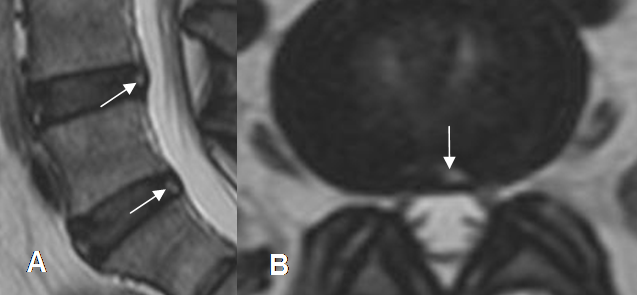

Fig 42. Ruptura del anulus.

A: RM sagital en T2 y B: RM axial en T2. Hiperintensidad en la parte posterior del anillo fibroso, por fisura o ruptura de sus fibras.